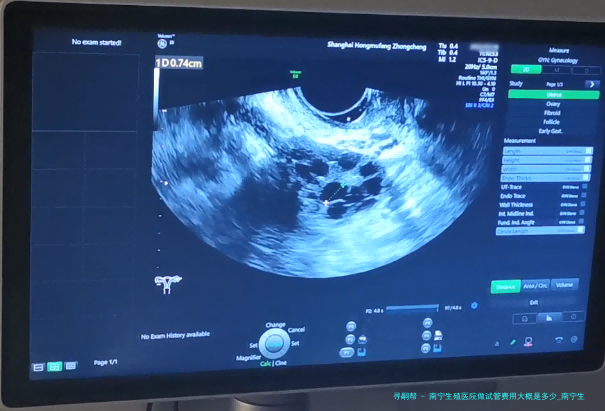

南宁生殖医院做试管费用大概是好多?试管婴儿已然成为许多不孕夫妻实现生育愿望的重要方法其中之一。南宁生殖医院作为专门从事辅助生殖医学的医疗机构,为不孕夫妇提供了精良的试管婴儿服务。如此南宁生殖医院做试管费用大概是几何呢?接下来将细致说明。

南宁生殖医院作为一家专业从事辅助生殖医学的医疗单位,提供了全面而专业的试管婴儿服务。根据不同病人的详细情况和需要,试管费用可能会有所差别。通常来说,南宁生殖医院做试管的基本治疗费大约在5000-10000元之间。辅助检查和药物费、手术设备使用费、麻醉师操作费等其他费用视详尽情形而定。